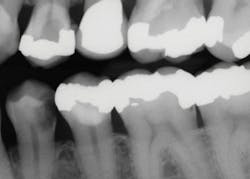

Often, it is difficult to estimate the vitality of teeth in older patients who have significantly receded pulps, or in patients of any age who have deep caries (figure 1). Teeth with minimal pulp tissue visible on the radiographs can be either nonvital and necrotic or in the process of becoming nonvital—you cannot determine that condition from radiographs. The trauma of tooth preparation and restoration placement can stimulate a painful condition for patients, even in relatively shallow tooth preparations.

Figure 1: The mandibular first premolar tooth has caries that could be a pulp exposure. The maxillary first premolar has an apparent pulp exposure, but the caries could be facial or lingual to the pulp. Both teeth should be excavated carefully as described in this article to determine the status of the caries.